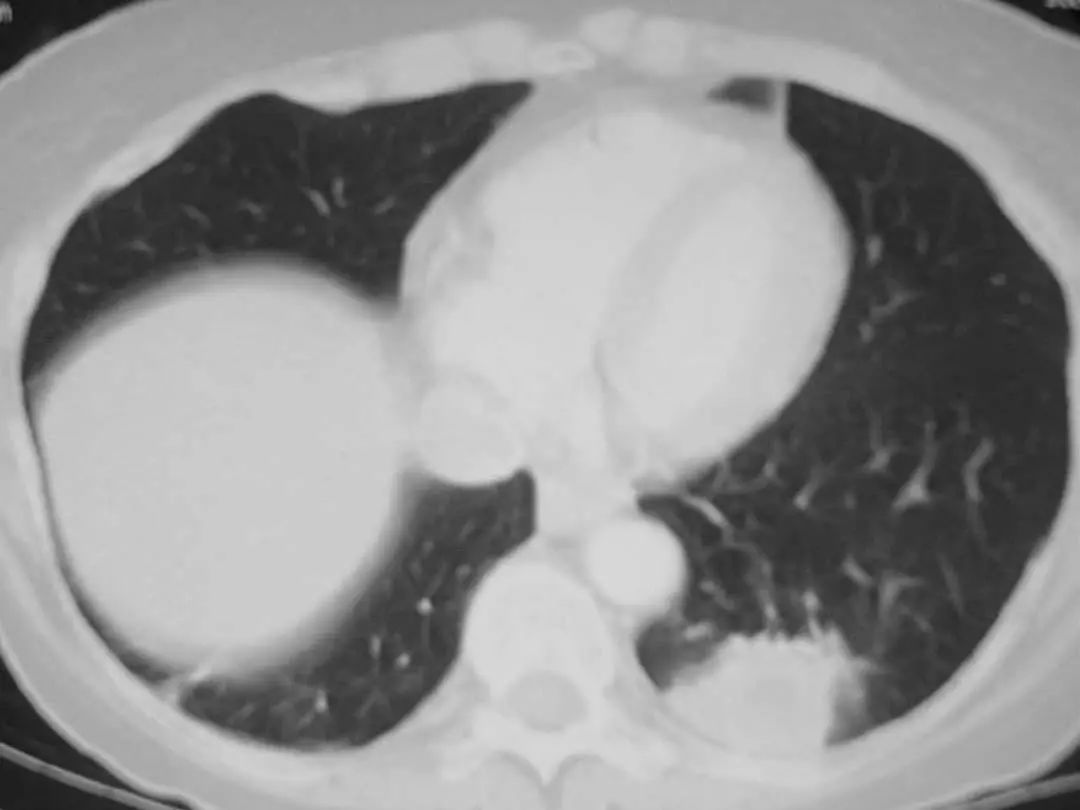

图1.9 49岁肺炎球菌性肺炎患者, 胸部X线片显示左下叶不透明伴胸腔积液。

图1.10 48岁的流感嗜血杆菌性肺炎患者, 胸部X线片显示双侧不透明,主要分布在外周。

图1.11 49岁的肺炎球菌性肺炎患者, 胸部CT显示左上叶不透明延伸至外周。

图1.12 50岁流感嗜血杆菌肺炎患者胸部CT。显示左下叶胸膜附近有致密圆形实变。